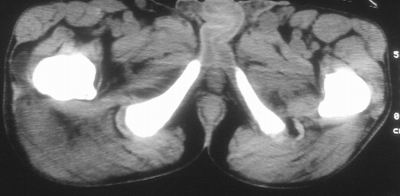

患者,男,63岁,自诉3个月前发现右臀部包块,触及疼痛,治疗后缩小。前天突然增大。无高热病史。

考虑-----右臀大肌,臀中肌---感染性病变可能性大。

病灶内部可见出血,首先考虑急性出血性病变.血肿?

给个骨窗,判断一下肿块是否与髂骨有关,肿块内出血是肯定的,至于是感染形成的脓肿还是起源于肌肉或纤维组织的肉瘤则难以确定,不过从影像上看,包膜完整,且环形增厚,病灶下部见斑片状底密度坏死,个人倾向感染可能性大

肌间隙明显混浊,三个月前治疗有缩小,支持考虑臀大肌下脓肿伴出血,肿瘤如果出现瘤内出血的话瘤外边界应该较清楚,现在表现为一种恶性征像,但骨质无明显异常,且臀小肌边界清楚,不符合恶性表现.